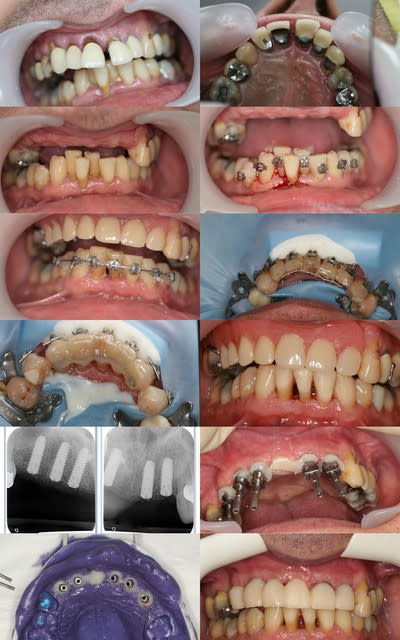

un cas mutlidisciplinaire

voila je suis en vacances et je voulais vous faire un petit cadeau avant départ si vous êtes sages au retour on détaillera ce travail qui m'a pris un peine plus de douze séances ... enfin parfois je mens aussi ...(en fait 15 je crois )

restera deux séances pour la pose du travil conventionnel comme quoi nous aussi on peut faire comme les low coaster :-))